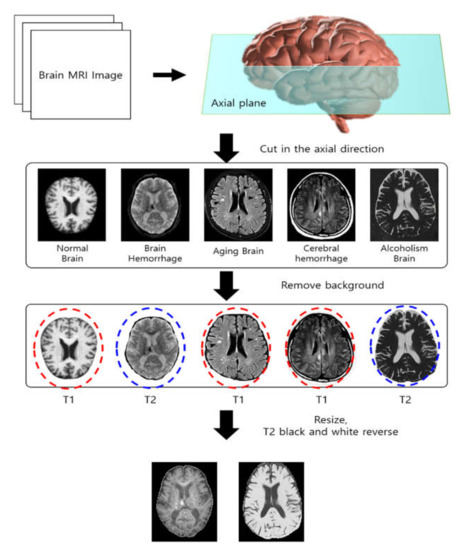

The data used in this study are the brain images and patient information data according to the dementia stages provided by OASIS. In the patient information data, preprocessing is made; e.g., the removal of unnecessary variables, etc., and, with the clinical dementia rating as the dependent variable and other variables as independent variables, regression analysis is conducted. The brain condition related to MMSE is recollected and extracted accordingly, and, unless the size of the collected image and that of the recollected image are the same, there may be an error in the CNN operation. Thus, all images are adjusted to the same size to transfer the style. In addition, the weighted value of the content image in the model is that of the clinical dementia stage, and 0 means non-demented; 0.5, very mild; 1, mild; 2, moderate. To prevent the transfer of information about unnecessary attributes, the background of all images is removed before proceeding. The development environment of the research is hardware AMD Ryzen 9 5900X 12-Core Processor 3.70 GHz, 64GB RAM, GeForce RTX 3090(NVIDIA). In addition, as a software environment, Python 3.7 and Anaconda 4.5.11 are employed. The performance evaluation makes a comparison with similarity to the image transferred in style according to the dementia rating. Figure 7 shows the data processing process for performance evaluation.

Figure 7.

Data processing process for performance evaluation.

The data processing process for performance evaluation in Figure 7 generates MRI data that cut the brain on the axial plane. Accordingly, unnecessary backgrounds are removed, leaving a part of the brain where each character can be identified. Finally, the remaining image data unify T1 and T2. In the case of T1, the water component appears in black, and the fat component appears in white. Alternatively, in the case of T2, contrary to T1, the water component appears white, and the fat component appears black. Therefore, in order to unify this, in the case of T2, black and white are reversed so that the same characteristics as in T1 are displayed. Further, the size of the image is created to be the same as 110 × 150. Accordingly, images are processed under the same conditions, the results are extracted through the proposed model, and a performance evaluation is performed.